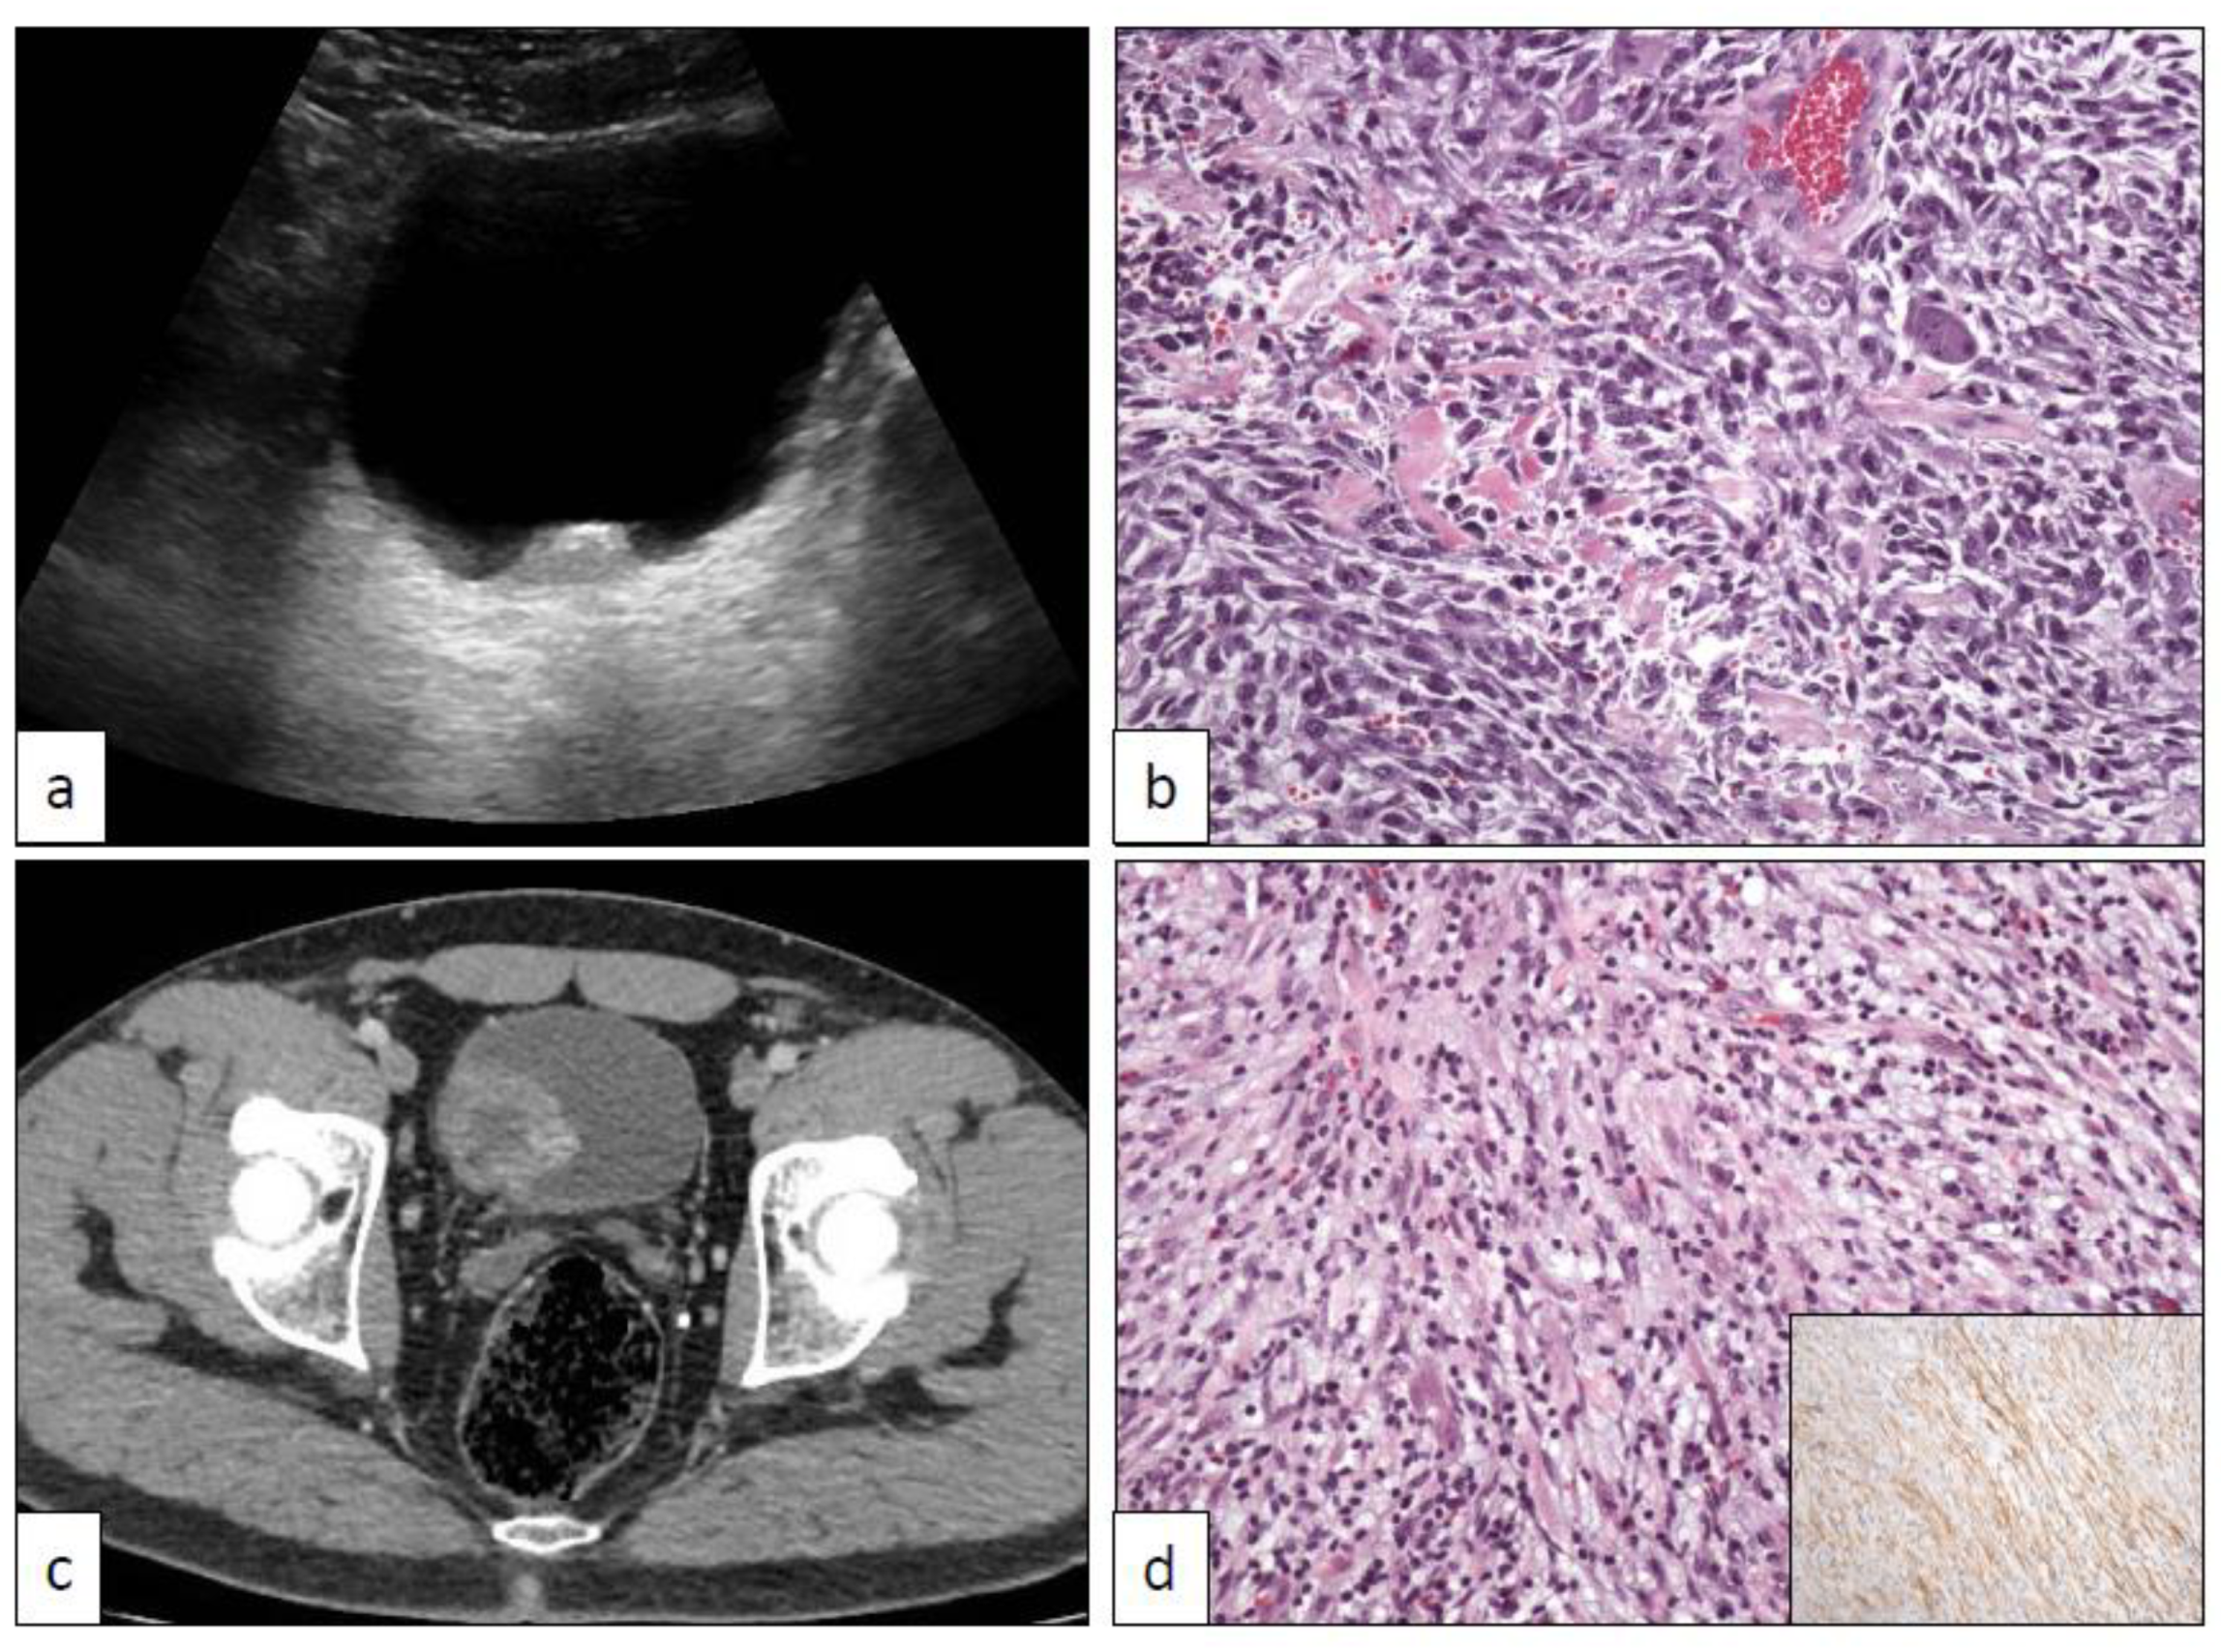

16. PEComa (PEC)

17. Pseudosarcomatous Myofibroblastic Proliferations